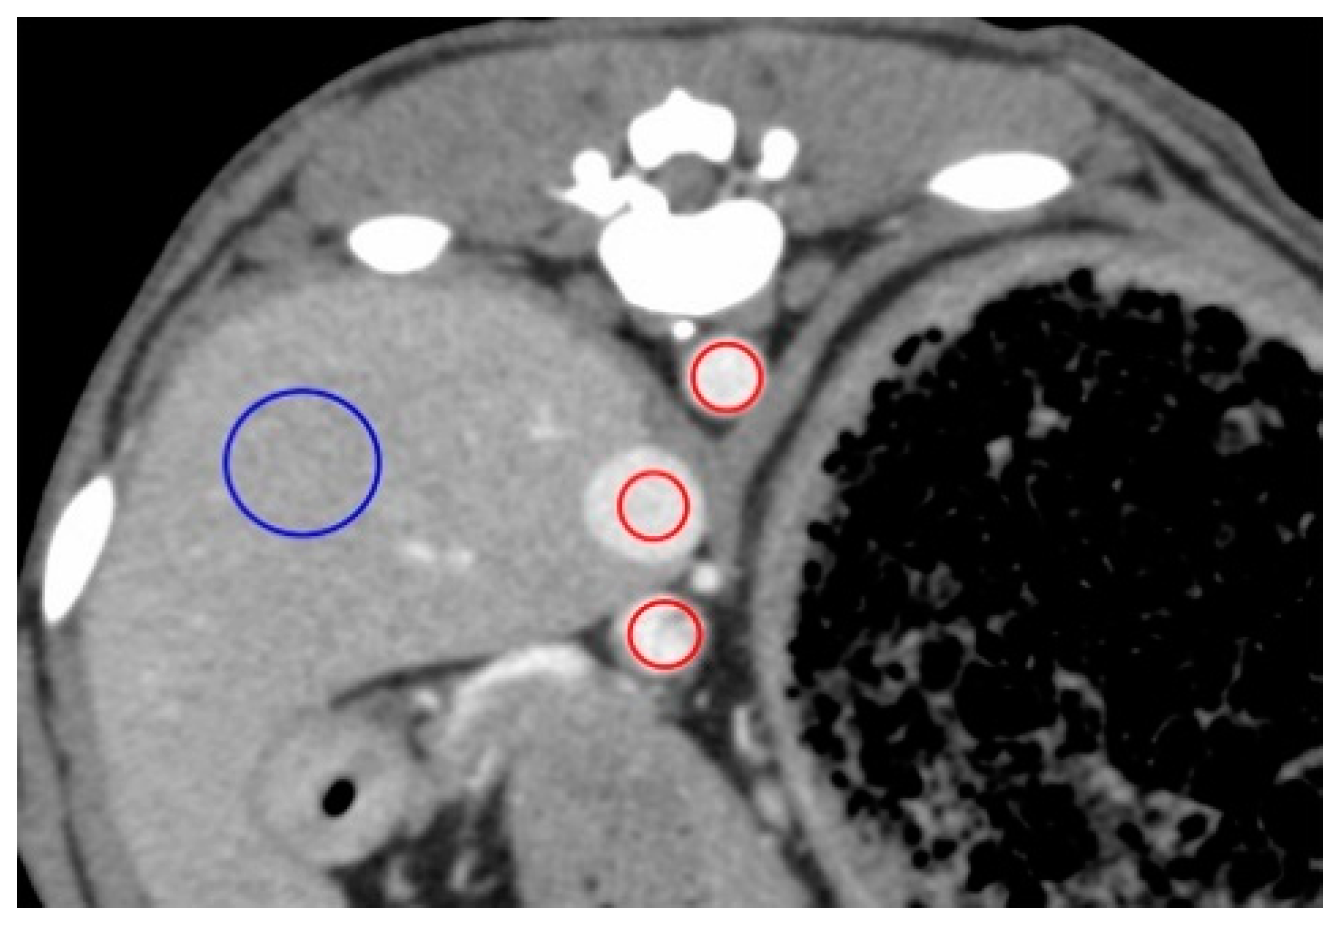

All CT images were reviewed on a dedicated DICOM viewer (OsiriX MD, Pixmeo SARL., Bernex, Switzerland). Contrast enhancement measures were obtained at the following regions of interest (ROIs; Figure 1): 40 mm2 area at the center of the AO, PV, and CVC, and a 200 mm2 area in either the left of right lateral lobe of the liver for HP measures, avoiding the hepatic vessels. All measures in the regions of interest (ROIs) were recorded in Hounsfield units (HU). The following time-based parameters were also measured from the time of contrast medium injection: first appearance of AO enhancement (AO-EA) and the AO enhancement peak (AO-EP); first appearance of CVC enhancement (CVC-EA) and the CVC enhancement peak (CVC-EP); first appearance of PV enhancement (PV-EA) and the PV enhancement peak (PV-EP); and first appearance of HP enhancement (HP-EA) and HP enhancement peak (HP-EP). The time-attenuation curve (TAC) was calculated based on all measured values in the ROIs.

Figure 1. Measurement of the contrast values for the hepatic vessels and hepatic parenchyma on a representative image obtained 50 s after injection for the anesthesia protocol. The contrast values of the aorta (AO), caudal vena cava (CVC), portal vein (PV), and hepatic parenchyma (HP) were measured by placing the region of interest (ROI) in the center of the AO, center of the CVC, the center of the PV, and right lateral lobar parenchyma, respectively. ROIs demarcated by red lines have an area of 40 mm2 and those in blue have an area of 200 mm2.